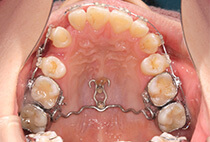

治療後

しっかり前歯を下げるために、インプラントアンカーを使用してコントロールしました。

かみ合わせが整い咬筋の過緊張も改善しました。咬筋の肥大も治ってフェイスラインがすっきりしました。

最終的には美しい歯並びと、安定した痛みのないかみ合わせが実現しました。